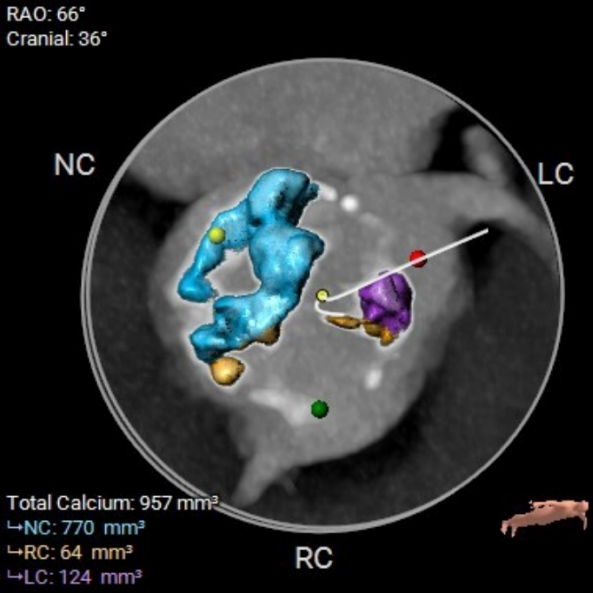

主动脉瓣瓣环周长85.4mm,周长径27.2mm,LVOT 28.1mm,STJ 29.4mm。CT数据分析显示该患者为Type1型二叶瓣,瓣叶重度钙化且增厚,主要分布于无冠瓣叶,左冠窦有团状钙化并延伸至左室流出道,HU850:957mm²。

左冠开口高度13.0mm,右冠开口高度16.5mm,双侧冠脉开口未见明显附壁钙化,结合瓦氏窦宽度和瓣叶长度综合判断冠脉阻挡风险较低。